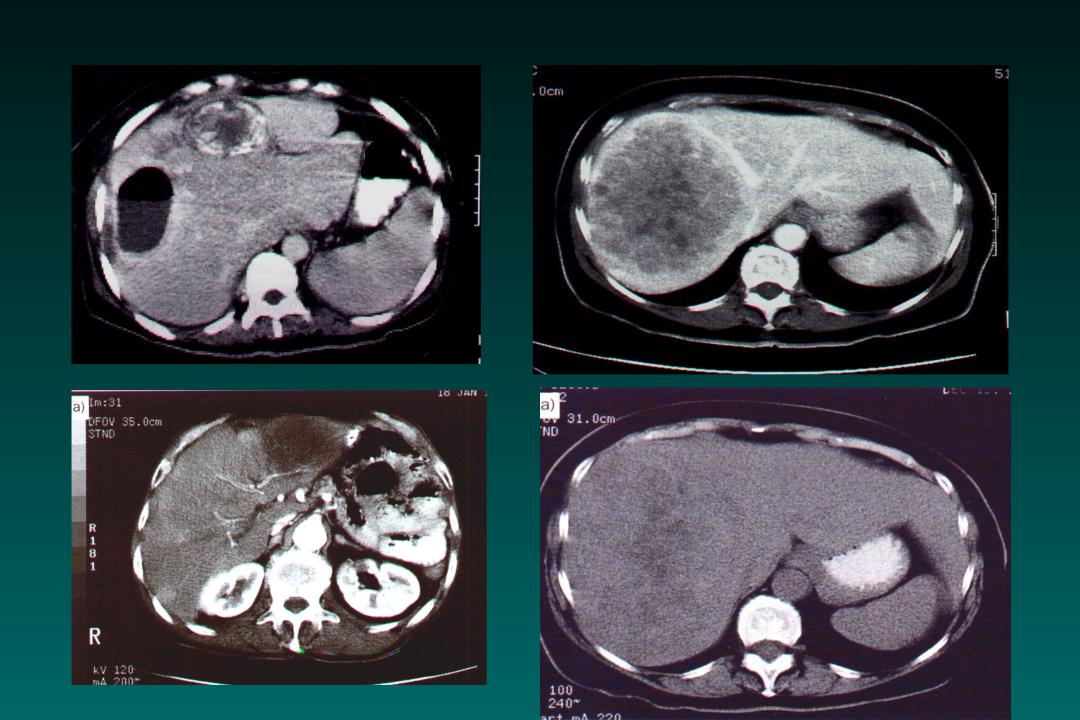

КТ диагностика тубоовариального абсцесса: Подходы и изображения

Раздел: Объективный взгляд